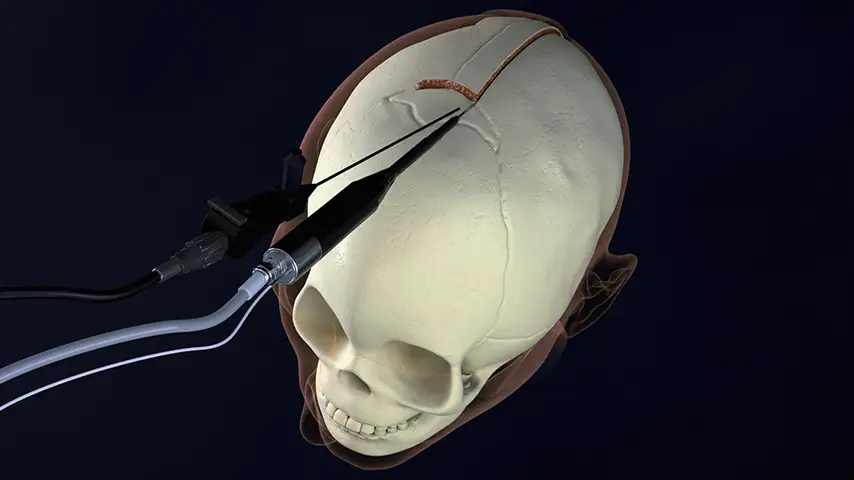

Craniotomy

and craniectomy

Endoscopic strip craniectomy

PIEZOSURGERY® plus

PIEZOSURGERY® plus is the complete device: it is engineered to support an expansive range of surgical applications in Neurosurgery.

Unmatched efficiency, precision, and performance delivered through two independent handpieces and channels.